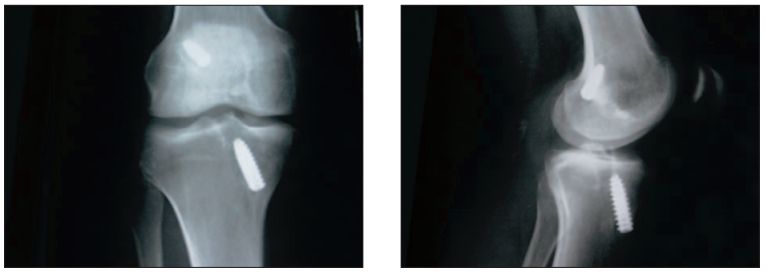

Zabieg rewizyjnej rekonstrukcji więzadła krzyżowego przedniego (ACL) przeprowadzono u 32 letniego pacjenta, u którego w 5 tygodniu po artroskopowej rekonstrukcji ACL doszło do ponownego urazu i zerwania przeszczepu autogenicznego. Nawrót niestabilności objawiał się dodatnim testem szufladowym przednim oraz dodatnim testem Lachmana.

Przy istniejącej niestabilności przedniej stawu kolanowego na zdjęciach radiologicznych stwierdzono prawidłowo przebiegające kanały kostne, co świadczyło o śródstawowym uszkodzeniu przeszczepu autogennego. Zaplanowano wykonanie zabiegu rewizyjnego z wykorzystaniem istniejących kanałów kostnych z użyciem allograftu z więzadła rzepki.

Po opracowaniu końców kostnych przeszczepu nasączono allograft w żelu płytkowym. Po wprowadzeniu allograftu pod kontrolą artroskopu do kanałów kostnych umocowano go tytanowymi śrubami interferencyjnymi firmy Medgal. Uzyskano stabilny staw kolanowy w pełnym zakresie ruchu. Ocena wgajania przeszczepu prowadzona była na postawie badania rezonansu magnetycznego. Badanie wykonano w 6 i 12 tygodniu po zabiegu.